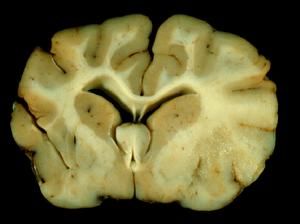

病理

腦白質主要由神經纖維構成,有髓纖維由軸突髓鞘和Schwann細胞構成,髓鞘基本為同心環狀纏繞的雙層單位膜,髓鞘是神經纖維的主要組成部分,具有保護和營養神經纖維作用,任何原因的髓鞘異常均可引起臨床發病。

腦白質對各種有害刺激的典型反應是髓鞘的變化,髓鞘的異常改變是腦白質病影像表現異常的基礎,脫髓鞘病變是一種髓鞘正常形成和被供養維持後又被內源或外源致病因素破壞的疾病,主要累及腦深部白質,腦室周圍,其病理改變認為與腦室周圍白質髓鞘含量降低,室管膜細胞丟失,側腦室前角附近膠質增生,室管膜周圍間隙細胞外液含量增加及軸突變少有關。

MRI是顯示腦白質及白質病灶最敏感的方法,以T2加權像更為敏感。除橫斷位外,還應包括冠狀斷掃描,有些病理變化僅在冠狀斷T2加權像上才能充分顯示。T2加權像顯示的髓磷脂沉積過程與屍檢切片髓磷脂染色所見,相關良好。在矢狀斷像上,MRI可顯示腦幹腦白質的發育情況。若常規掃描發現腦白質信號異常,可行增強掃描,以確定病灶的嚴重程度、活動性和進行鑑別診斷。